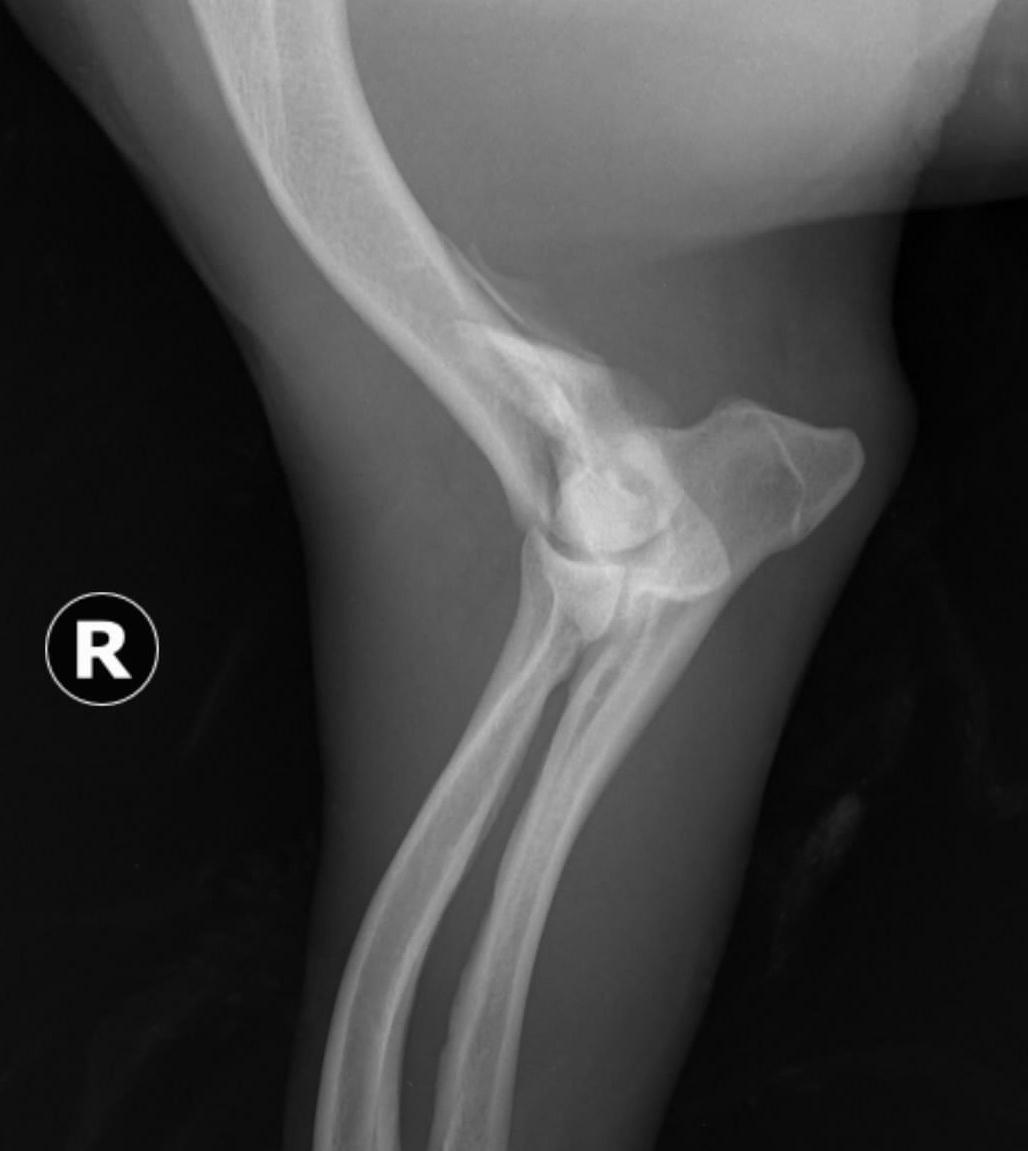

Validarea poziționării corecte a plăcii în raport cu osul și a selecției adecvate a dimensiunii și numărului șuruburilor s-a realizat prin examen imagistic radiografic convențional, utilizând incidențele clasice, respectiv incidența medio-laterală și incidența cranio-cau -

Figura 12. Punctele de reper și poziția câinelui pe masa de operație pentru abordul minim invaziv al femurului - a)Trocanterul mare al femurului. b) Condilul lateral al femurului. c) Patela. d) Poziția femurului și orientarea lui pe masa de operație

dală (figura 17). Aceste investigații au relevat că spațiile articulare proximal (acetabul - cap femural) și distal (condilii femurali lateral și medial - platou tibial) au rămas nemodificate. Patela și oasele sesamoidiene au rămas integre și nu s-au înregistrat modificări ale poziției acestora.

Figura 17. Imaginea radiografică a coapsei după fixarea plăcii – incidență cranio-caudală (a) și medio-laterală (b).